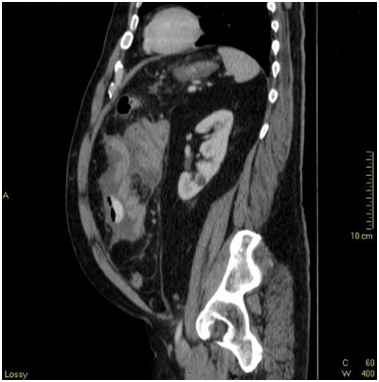

Admission labs showed a slight elevation in alkaline phosphatase, platelets and white blood cell count. There were no other major laboratory abnormalities and/or signs of infection. CT scan showed compartmentalized interloop hypodense fluid collection throughout the mesentery with associated fat stranding and small mesenteric nodules. (Images 1-3) There was encasement of small bowel loops, pleating of the mesentery and contraction of the peritoneal cavity. Mild small bowel dilatation without obstruction also noted.

CT scan is the main diagnostic tool with two distinct patterns on cross sectional images: (a) diffuse involvement of the peritoneal cavity and (b) focal intraperitoneal masses. Our patient presented with diffuse involvement of the peritoneal cavity without omental caking or masses. Small bowel encasement with interloop fluid and radial small bowel distribution was noted, as well as "stellate" mesentery due to tumoral infiltration. (Image 1,2,3) Differential diagnosis from imaging standpoint includes peritoneal infections such as tuberculosis, histoplasmosis and peritoneal carcinomatosis.6